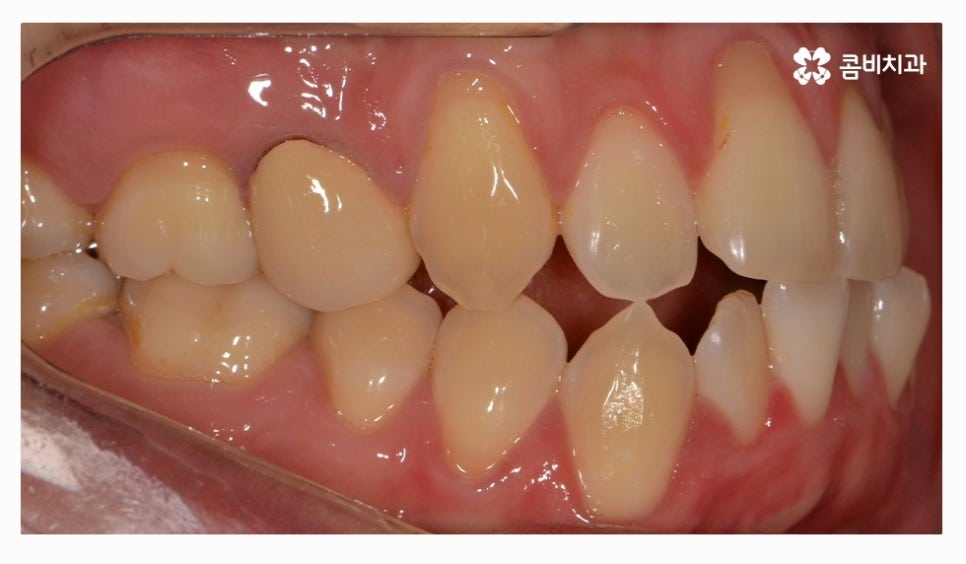

오늘 소개드릴 환자분은 윗니와 아랫니가 제대로 맞물리지 않는

부정교합 사례이며 클리피씨교정을 통해서 치료가 진행된 사례라고 할 수 있어요.

부정교합 환자분들의 경우 발치나 수술이 필요한 경우가 있는데

치아교정을 진행할 때 치아의 이동 공간을 고려해야 하므로

치간 삭제나 어금니 후방 이동으로도 치아 이동 공간이 부족하다면

발치를 필수적으로 해야 하는 경우가 있어요.